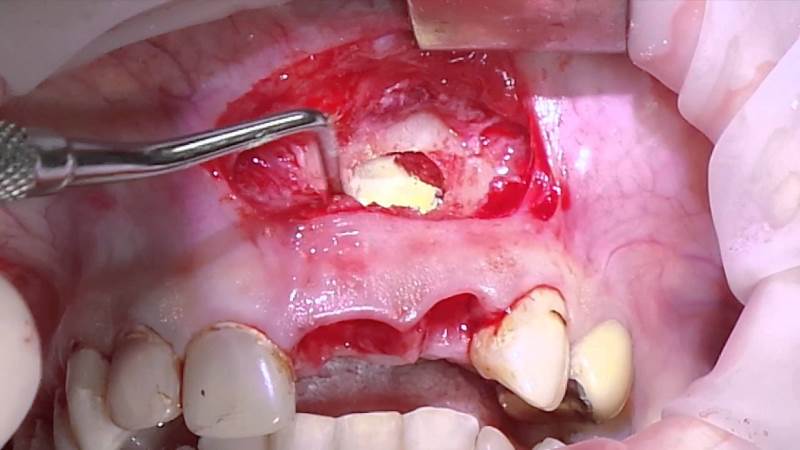

Если после выполнения процедур киста в челюсти продолжает расти, применяется апикальный хирургический метод лечения.

В ходе этой операции хирург удаляет содержимое кистозного образования, а затем извлекает корневую часть зуба, которая была поражена инфекцией. После этого производится пломбирование изнутри, и разрез сшивается. В случаях, когда, например, киста зубов нижней или верхней челюсти возникает повторно, может потребоваться удаление зуба с последующей установкой имплантата. Современные стоматологические технологии предлагают различные решения проблемы, позволяя сохранить зуб при возможности.